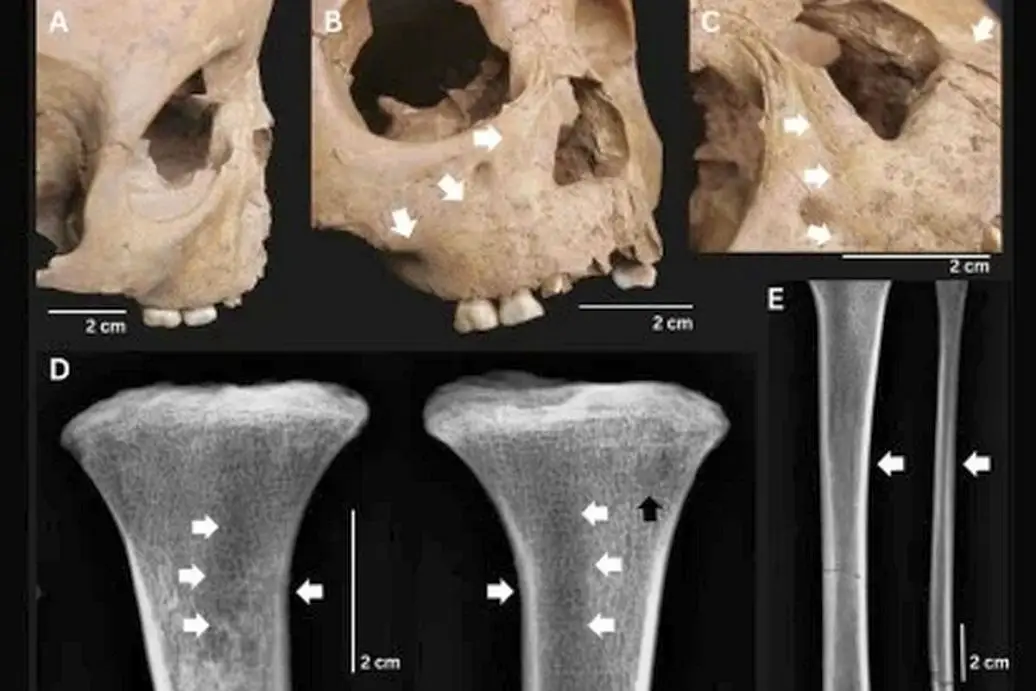

Останки пятилетнего ребенка из памятника Ман-Бак со следами болезни (на фото указаны стрелками)

Археологи решили, что это какая-то случайность. Но вскоре в том же Ман-Баке они извлекли из земли скелет пятилетнего ребенка. У маленького древнего индокитайца был деформирован нос, а на отростках верхней челюсти и берцовых костях патологически разрослась костная ткань. Это организм пытался защититься от инфекции, но делал это хаотично и слабо.